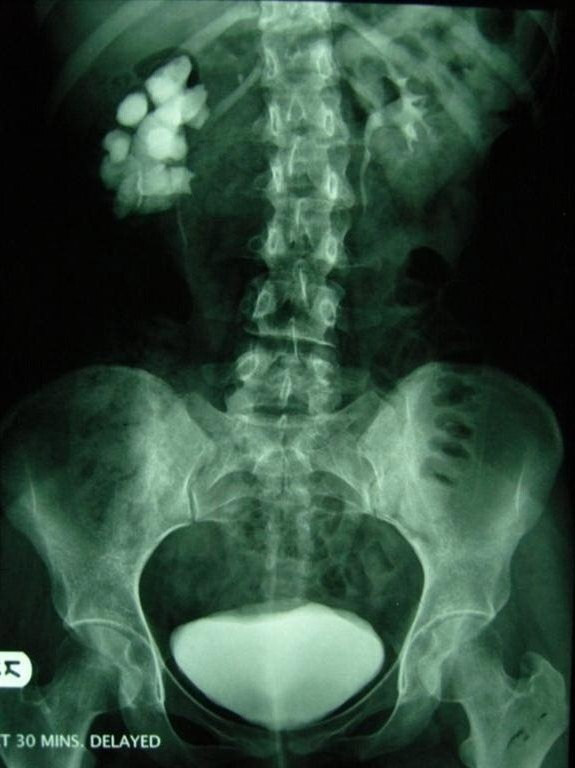

Neden leğen kemiği kayar?

Femur kemiğinin origosunun baş kısmı kendi yuvasından aşağıya ya da yukarı doğru kayıyor.Bu kayma sonucunda pelvis kemiğinin yanaklarından biri kayma sonucunda eğim kazanıyor.Eğim gerçekleştiğinde sacrumdan başlayıp lumbal bölgeyi ve sonrasında tüm vertebra disklerini kendi eksenlerinde döndürüyor.

Disklerin içi sıvı kıvamında ve dışa doğru koyulaşıp kabuklaşan bir yapıdadır,bu sayede kolay şekil değiştirebilir. Yukarıdan aşağıya bastırılan yüklerin bir tarafa eğik basması halinde bile bu yumuşaklık sayesinde bir alta yükü eşit dağıtır.Ani ve ters yüklenmeler sonucunda vertebra diskleri intervertebral disk kıkırdağının (pulpeus) etrafında sağ sola hareket edebiliyor.Bir disk döndüğünde nerelere zarar veriyor bunu bir disk kaydığında neler olur butonuna tıklayarak öğrenebilirsiniz